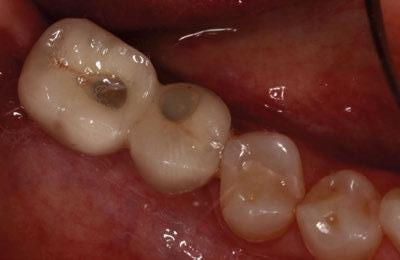

A los 4 meses, se retiró la prótesis provisional, verificando la